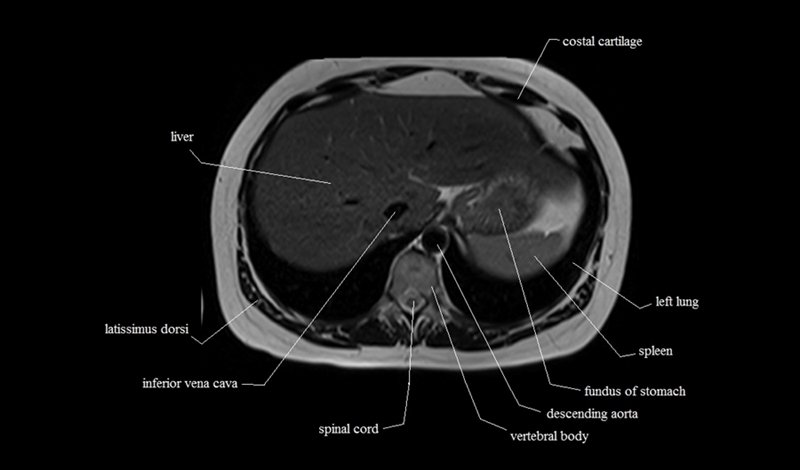

MRI Axial Cross Sectional Anatomy of Chest

This MRI chest (thorax) axial cross sectional anatomy tool is absolutely free to use. Use the mouse scroll wheel to move the images up and down, or alternatively, use the tiny arrows (→) on both sides of the image to navigate through the images. For a more detailed view, double-click the image to view it in full screen, and use the menu in the top right-hand corner to view individual slides or play them in a loop.